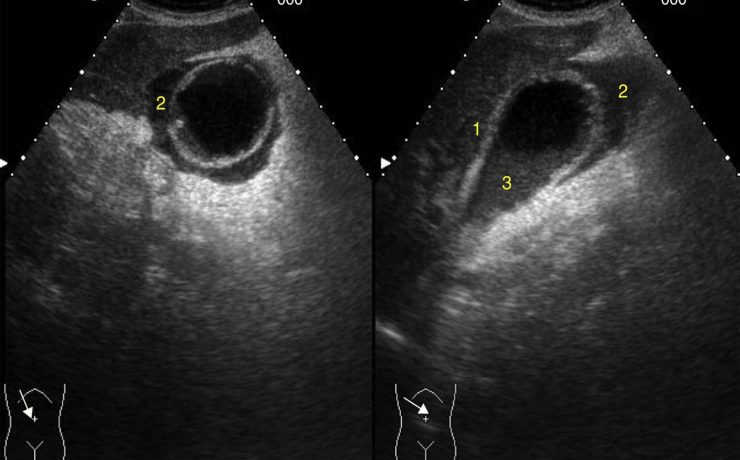

Rotura uterina por acretismo placentario

La rotura uterina durante el embarazo es una de las complicaciones más graves, que aumenta la morbilidad y mortalidad materna y fetal. La rotura uterina por placenta percreta es rara. La rotura uterina es cualquier desgarro, fracción o solución de continuidad supracervical en el útero que sucede durante el embarazo,